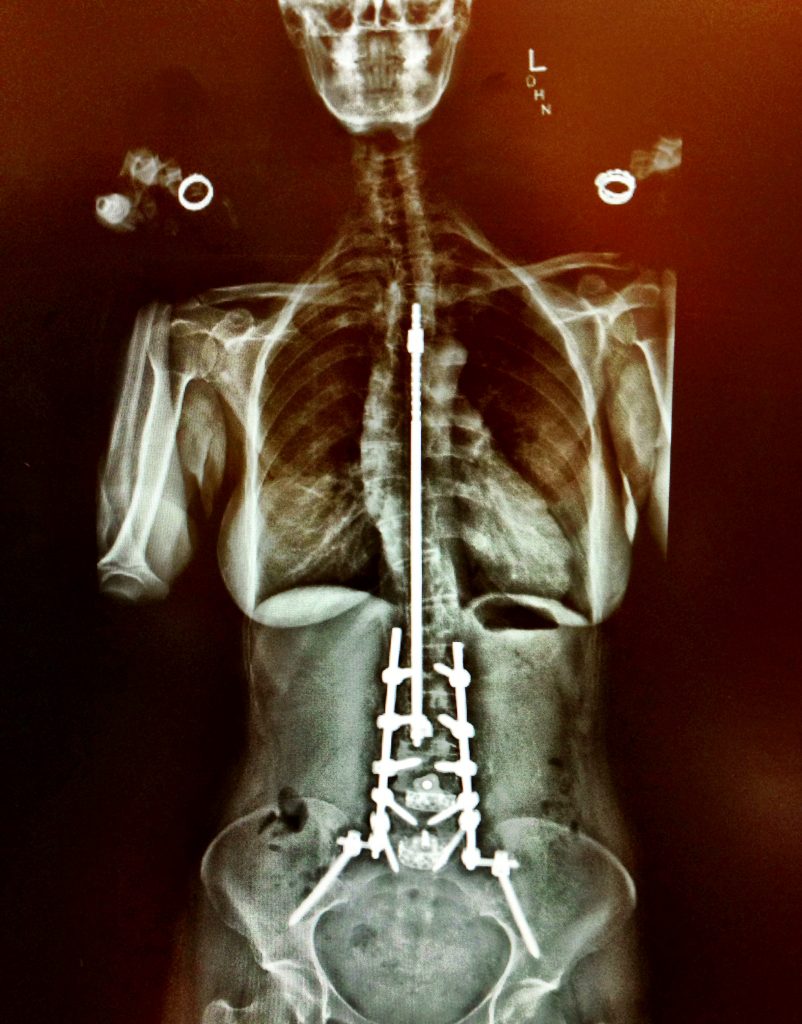

I had adolescent onset scoliosis, which was 1st treated as a teenager with the Harrington Rod. I've had 2 kids and thousands of miles ridden across the USA. 20 years later, I needed a second surgery for correction w/ Dr. Boachie for adult deformity scoliosis/kyphosis to relieve chronic pain, which was a huge success. Dr. Jeffrey Ngeow was a prince helping me through years of pain with brilliant pain management. I'm so grateful for my experience & outcome. Third surgery 6 years ago to correct additional deformity & pain. Still riding! Feeling fab. Now living the life in LA laughing, working out, hiking & riding.